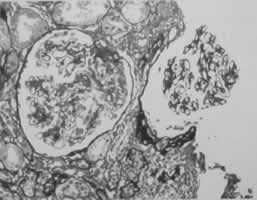

(3)支氣管鏡檢查 原因不明的咯血或支氣管阻塞肺不張的患者應考慮支氣管鏡檢查,如腫瘤、結核異物等,同時取活體組織病理檢查等。